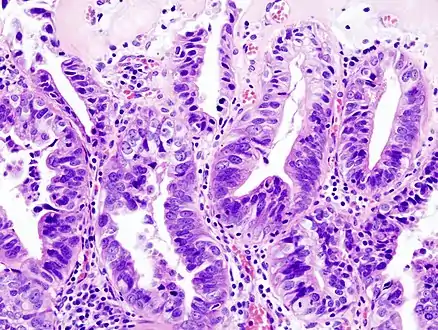

TypesAdenocarcinoma (most common), Squamous cell carcinoma (more rare)[3]

Most tumors are adenocarcinomas, with a small percent being squamous cell carcinomas.